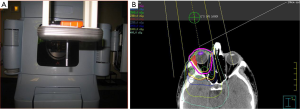

The radiation target volume need not include the whole orbit for conjunctival lesions. For other adnexal infiltrations and retro-orbital disease, the target volume includes the whole orbit. It is not necessary to cover regional lymph nodes or the contralateral orbit. For patients with conjunctival involvement and no retro-orbital extension, a single direct anterior field with either high energy electrons or photon energies ranging from 4mV to 6mV from a linear accelerator is sufficient. This technique is simple, reproducible and it also allows the option to provide shielding to the lens, anterior chamber, and the macula by suspending a 1 cm diameter cylindrical eye bar directly over the cornea (“pencil” eye shield) (Figure 4A). For electron beams, a similar eye shield of lesser thickness (1–1.5 cm, lead) can be used (51,56,57). Shielding should only be considered if there is assurance on the clinical setup that the disease will not be shielded. When photons are utilized to target the conjunctiva, bolus should be used to provide adequate surface dose. A prescribed dose of 24–25 Gy delivered in 1.5–2.0 Gy fractions specified at Dnorm will result in a dose of 20–24 Gy to most of the retro-orbital tissues (Figure 4B). For patients with retro-orbital disease, IMRT or VMAT will achieve a homogeneous dose to the CTV. In this scenario, lens shielding is omitted to avoid shielding the retro-orbital disease. Care is taken to minimize dose to the brain. For patients requiring bilateral orbital radiation, lateral opposed fields are often preferred, or a 3-field technique with addition of an anterior field with shielding of the midline structures between the orbits. For situations with bilateral involvement of the conjunctiva, bolus is used with opposed lateral photon fields to provide buildup of the prescription dose at the conjunctival surface.